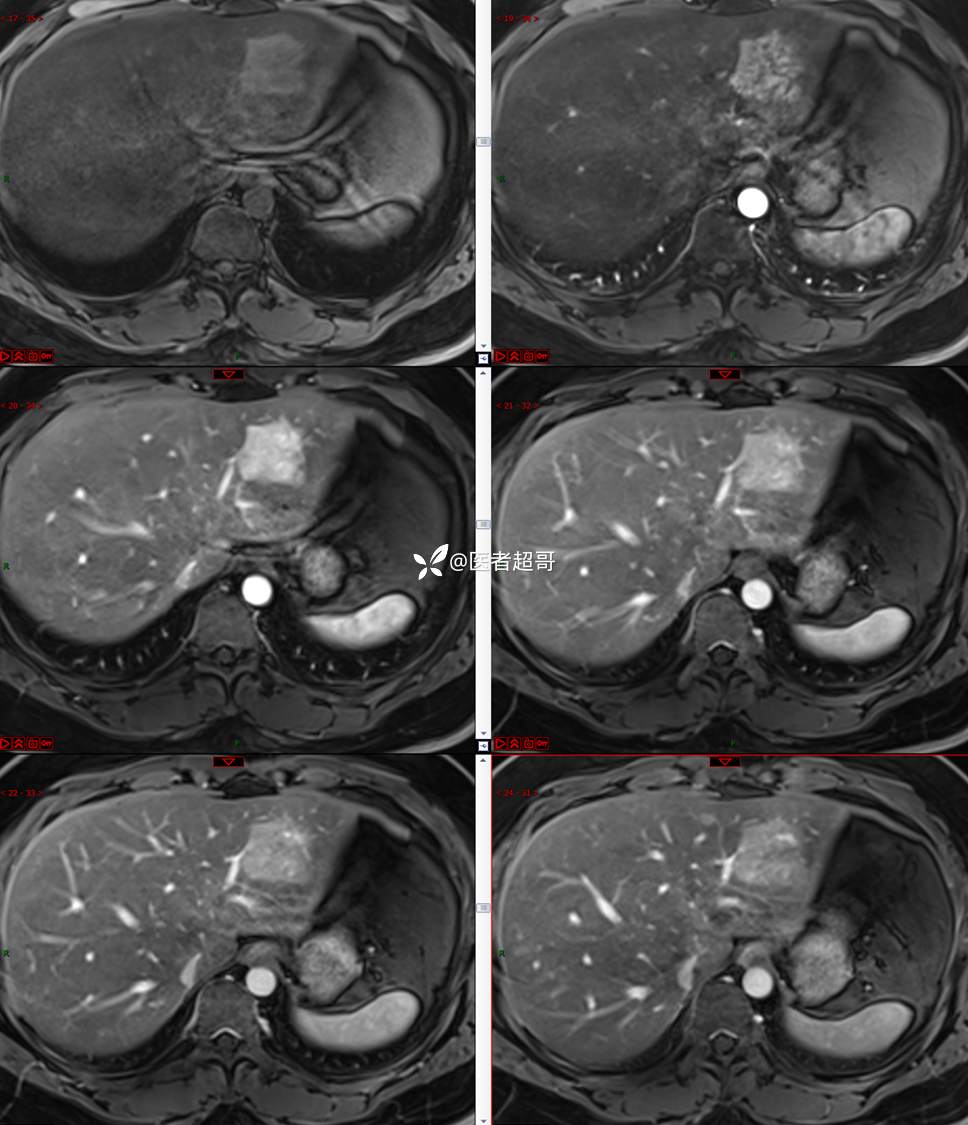

【影诊笔记685】男,31y,发现肝占位性病变5天就诊,请诊断分析,有病理结果!

主 诉:发现肝占位性病变5天。

现病史:患者缘于5天前体检时发现肝占位性病变,未予以特殊处置。现患者为求系统诊治就诊于我院,行普美显提示:肝左叶富血供占位,请结合临床及其他检查,肝多发血管瘤,脂肪肝,肝囊肿,请结合临床。门诊以“肝占位性病变”收入我科。病程中,饮食睡眠可,二便可,近期体重未见明显变化。